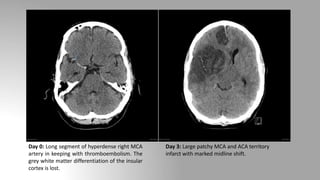

Day 0: Long segment of hyperdense right MCA

artery in keeping with thromboembolism. The

grey white matter differentiation of the insular

cortex is lost.

Day 3: Large patchy MCA and ACA territory

infarct with marked midline shift.

Day 0: Longsegment of hyperdense right MCA artery in keeping with thromboembolism. The grey white matter differentiation of the insular cortex is lost. Day 3: Large patchy MCA and ACA territory infarct with marked midline shift.